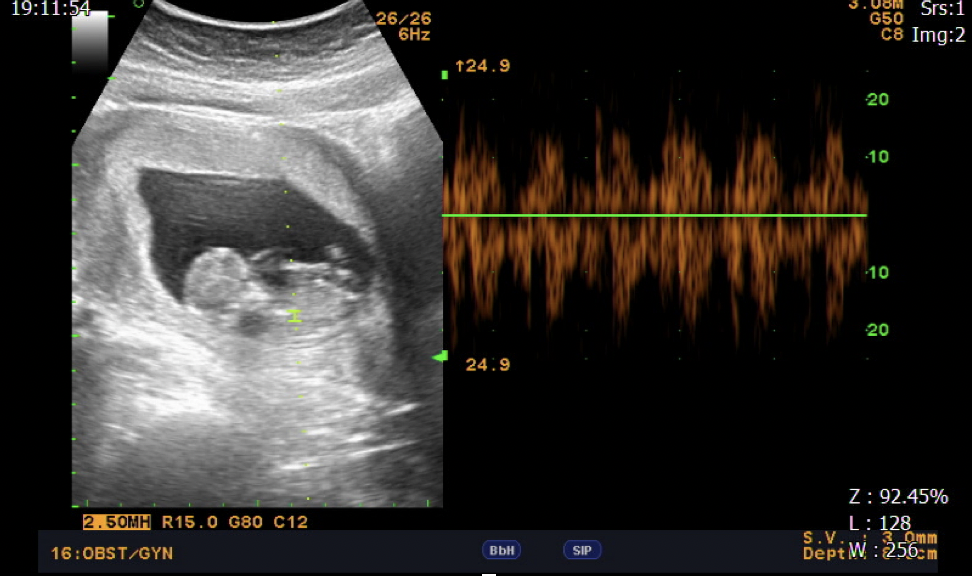

透過 MIRA新一代子宮內膜容受性檢測

我們發現B小姐的著床時間點比一般育齡女性的平均時間晚24小時

所以我們也將胚胎植入的時間點延後24小時